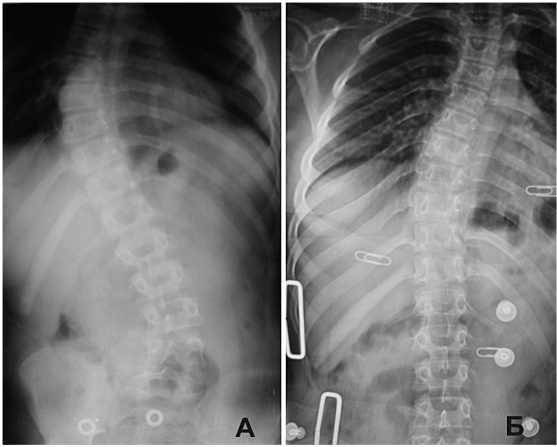

Пример №1. Пациент П., возраст 13 лет. Диагноз: ДЦП, спастическая диплегия. Комбинированный сколиоз III ст. Жалобы: Выраженные боли в нижней части грудной клетки справа по средне-ключичной и подмышеч­ной линии и в поясничном отделе позвоночника. На рис. 1 (А - Без кор­сета, Б - в корсете) показана сравнительная рентгенография первичного корсетирования по методу Шено (Первая неделя применения, промежу­ток между снимками 5 мин.).

Рис. 1. Рентгенография позвоночного столба, пациент П